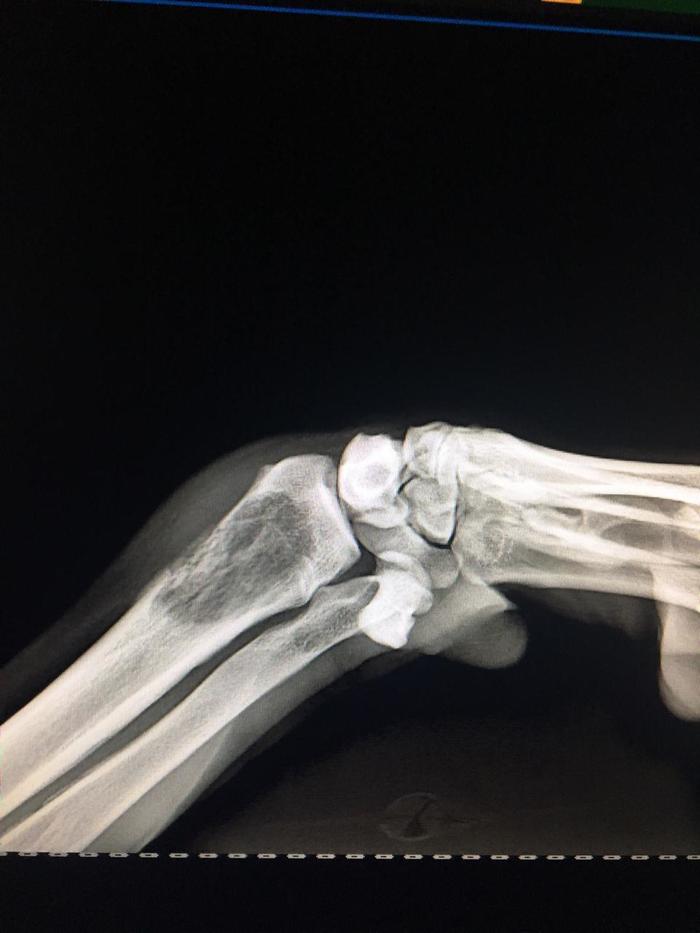

Заживала Умкина лапа хорошо, не смотря на разошедшиеся швы (ну да, остальные тоже разошлись, но мы уже не парились, не стали перешивать), все шло потихоньку. Он ходил на этом обломке былого величия вполне себе не плохо. Одна проблема, слишком короткая нога приводила к перекосу в нагрузке и было видно, что болит по вечерам. Приходилось делать массаж, но тут уж он конечно кайфовал, и через пару дней просек фишку, и уже приходил и заваливался с несчастным видом уже и днем, хотя явно все было норм, ведь за вкусняшкой летел как на крыльях.

На этой ноге он приспособился ходить очень быстро, даже бегал слегка, я правда не давала ему воли, мне до сих пор страшно что сломается эта палка титановая или кость, в которой она закреплена.